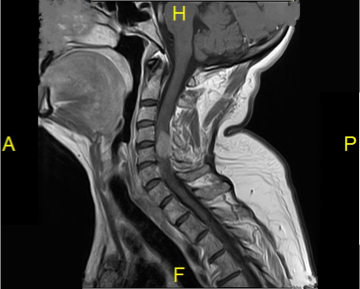

MRI of the cervical spine with and without contrast revealed a large (2.7x1.0x1.0 cm) enhancing intradural extramedullary tumor to the left of the midline at C4-C6 with dramatic compression of the spinal cord associated with spinal cord edema. Angiography revealed no significant hypervascularity, and metastatic work-up was negative. The appearance was consistent with a very large cervical meningioma. She was seen in consultation by multiple surgeons including surgeons at the state university hospitals and elected to undergo surgery with us.